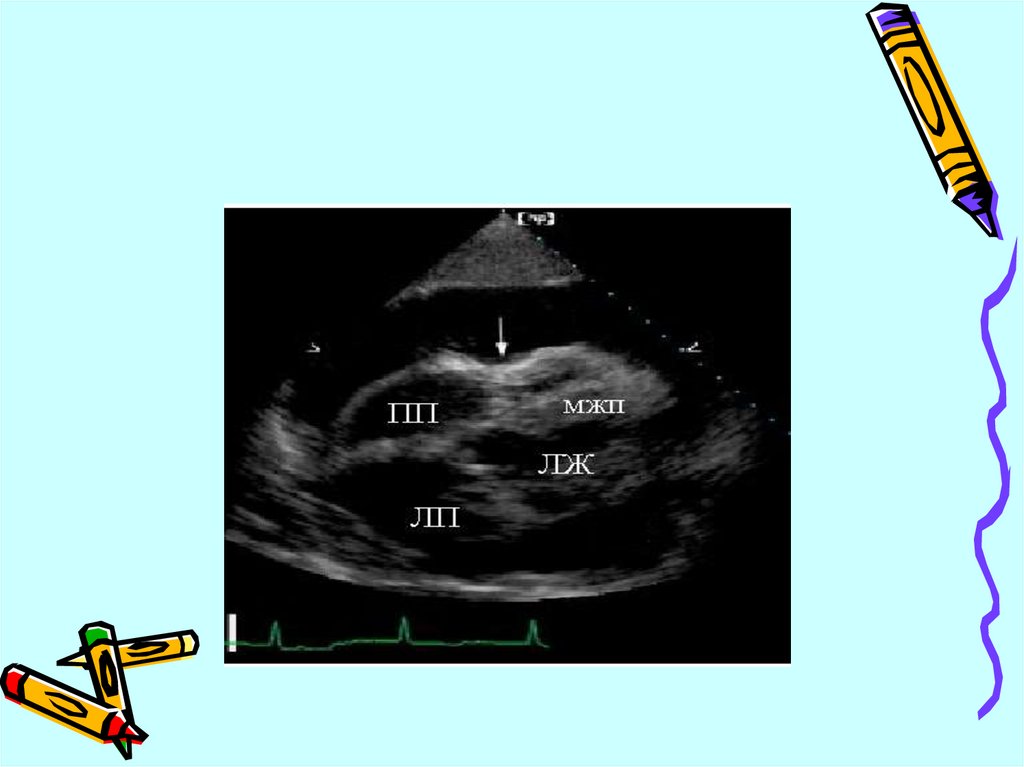

сократимости

Нарушение диастолической

функции